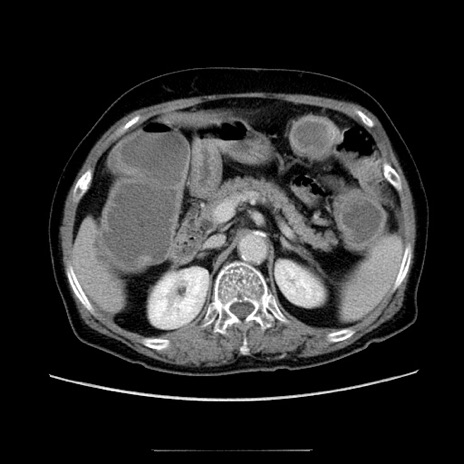

冠状断像

【症例】70歳代女性

【主訴】お腹が張る

【現病歴】1週間くらい前から腹部膨満の自覚あり。昨日夜から増悪したため、本日救急外来受診。

【身体所見】意識清明、BT 36.5℃、BP 165/106mmHg、HR 80bpm、SpO2 98%、腹部:膨満、軟、自発痛・圧痛なし、触診にて不快感あり、腸蠕動音:減弱

【データ】WBC 12600、CRP 1.04